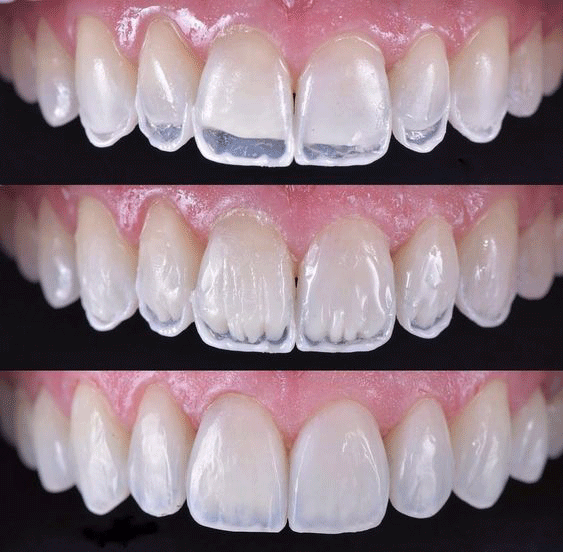

ونیر کامپوزیت با تکنیک لیرینگ(لبه شیشه ای)

کامپوزیت دندان به روش لیرینگ

یکی از ضعف های کامپوزیت دندان به صورت کلی در همه برند ها در طول زمان، مات شدن آن است، اما اگر کامپوزیت دندان به روش اصولی انجام شود این مورد نیز قابل رفع است. کامپوزیت دندان به روش لیرینگ بهترین روشی است که می توان به کار گرفت و از مات شدن کامپوزیت دندان در طول زمان جلوگیری کرد.

در روش کامپوزیت دندان به روش لیرینگ دندانپزشک مواد کامپوزیتی را لایه لایه روی دندان های شما کار می کند، که با استفاده از روش لایرینگ یا کاربرد کامپوزیت دندان با ترانسلوسنسی متفاوت در لایه های مختلف باعث شفافیت بالا و طبیعیتر شدن کامپوزیت دندان میشود.

کامپوزیت دندان به روش لیرینگ دقت و مهارت دندانپزشک را میطلبد، به صورت کلی اگر روش لایرینگ دندان و رعایت و بازسازی نسوج دندان به شکل ذاتی و طبیعی آن انجام شود 100% نتیجه نهایی هم لذت بخش خواهد بود.تکنیک لایرینگ و استفاده از ضخامت،طیف نوری، رنگ، ترنسلوسنسی و یا اپسیته متعارف و مناسب در هر لایه، ایجاد آناتومی ظریف و ایده آل و در آخر پولیش دندان مناسب، نتیجه پرفکتی ایجاد میکند که در طولانی مدت برای زیباجو خسته کننده نخواهد بود.

کامپوزیت دندان به روش لیرینگ لب شیشهای

امروزه در سلبریتیها، افراد معروف و بازیگران بهتازگی از لیرینگ لب شیشه ای یا به عبارتی کامپوزیت لبه شیشه ای یا لبه شفاف به روش لیرینگ دندان استقبال زیادی میشود و از آن برای زیبایی دندان خود استفاده می کنند.

با پیشرفت متدها در علم دندانپزشکی و روشهای جدید زیبایی و اصلاح طرح لبخند، متخصصان دندانپزشکی قادرند که عدم یکدست بودن دندانها را برطرف کرده و به آنها جلوهای زیبا و جذاب و در عین حال طبیعی ببخشند، به این منظور دندانپزشک از کامپوزیت هایی استفاده میکند که همانند ماده رزین دارای شفافیت و رنگهای متنوع باشند.

در واقع کامپوزیت لبه شیشه ای به روش لیرینگ دندان هم برای اصلاح طرح لبخند مورد استفاده قرار میگیرد و هم به صورت سلیقه ای برای زیباتر شدن و طبیعی تر جلوه دادن دندان ها مورد استقبال بسیاری قرار دارد که این مورد بستگی به سلیقه و انتخاب شما دارد. مطب دندانپزشکی دکتر ویسی در زمره اولین کلینیک هایی است که با استقبال فراوانی مواجه شد.